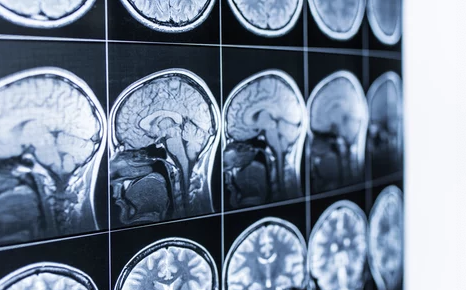

- 뇌 MRI / CT 영상 검사